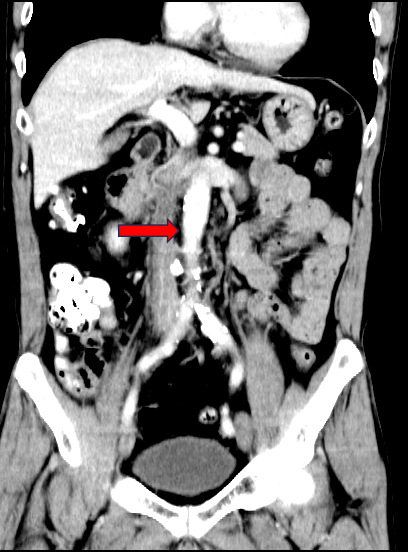

图为:入院CT及增强

图为:CT 三维重建

图为:入院全腹部CT及增强扫描